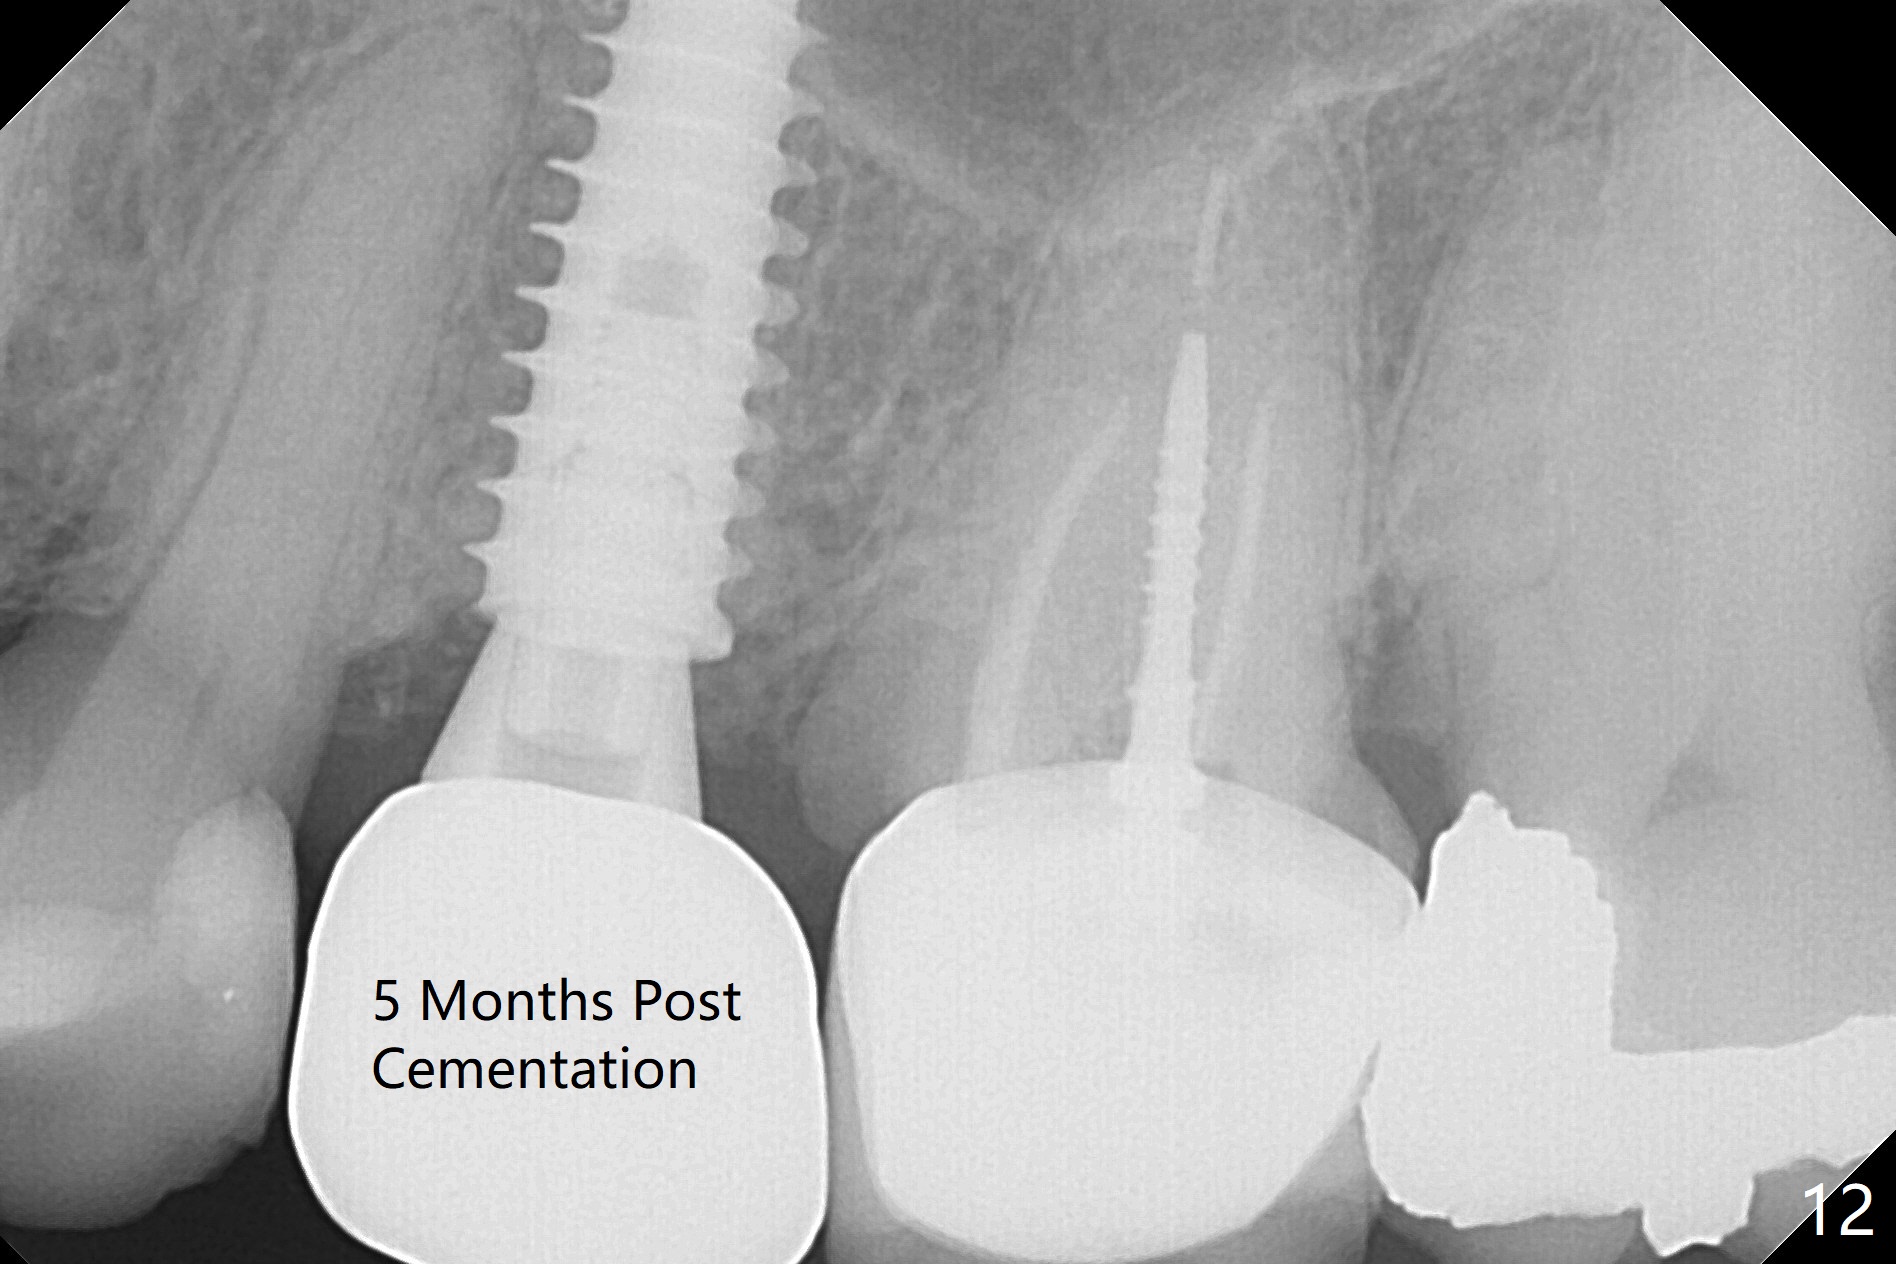

Since the apical native bone is limited at #13 after extraction, no PA is taken until a 4x11 mm dummy implant is placed after 1.6 mm and 3.3 mm drills for 13 mm (Fig.1). After using Lindamann bur to move the osteotomy distal and reusing 3.3 mm drill, the trajectory of a 4.5x11 mm IBS dummy implant improves (Fig.2,3 with low stability). When the implant is removed, the buccal portion of the socket is found to be perforated (Fig.4 P). Although the reason for the perforation is unknown, it is repaired by insertion of a piece of PRF plug, followed by allograft. #1 and 2 in Fig.4 represent the 1st and 2nd osteotomies, as shown in Fig.1 and 2, respectively. The trajectory of the final 5x13 mm implant is acceptable (Fig.5-7, different angulations), so is insertion torque (45 Ncm). After placing a 5.5x4(4) mm abutment, an immediate provisional is fabricated (Fig.8 P) with occlusal clearance (*). The interdental papillae remain in place 12 days postop (Fig.9 *). There is no sign of postop sinus infection. The provisional is loose 18 days postop; the abutment is changed to 5x4(3) mm (Fig.10). It is difficult to catch the mesial margin of the abutment for impression 4 months postop, due to poor oral hygiene and the short cuff (3 mm, Fig.11). The appointment for impression is rescheduled with emphasis on oral hygiene and no wearing the provisional for a few days prior to next appointment. Bone has grown into the space between the 1st and 2nd threads 5 months post cementation (Fig.12) and the bone is normal, solid and dense 2 years 11 months post cementation (Fig.13 >). There is mesial open margin of the tooth #14 (Fig.13,14 *).